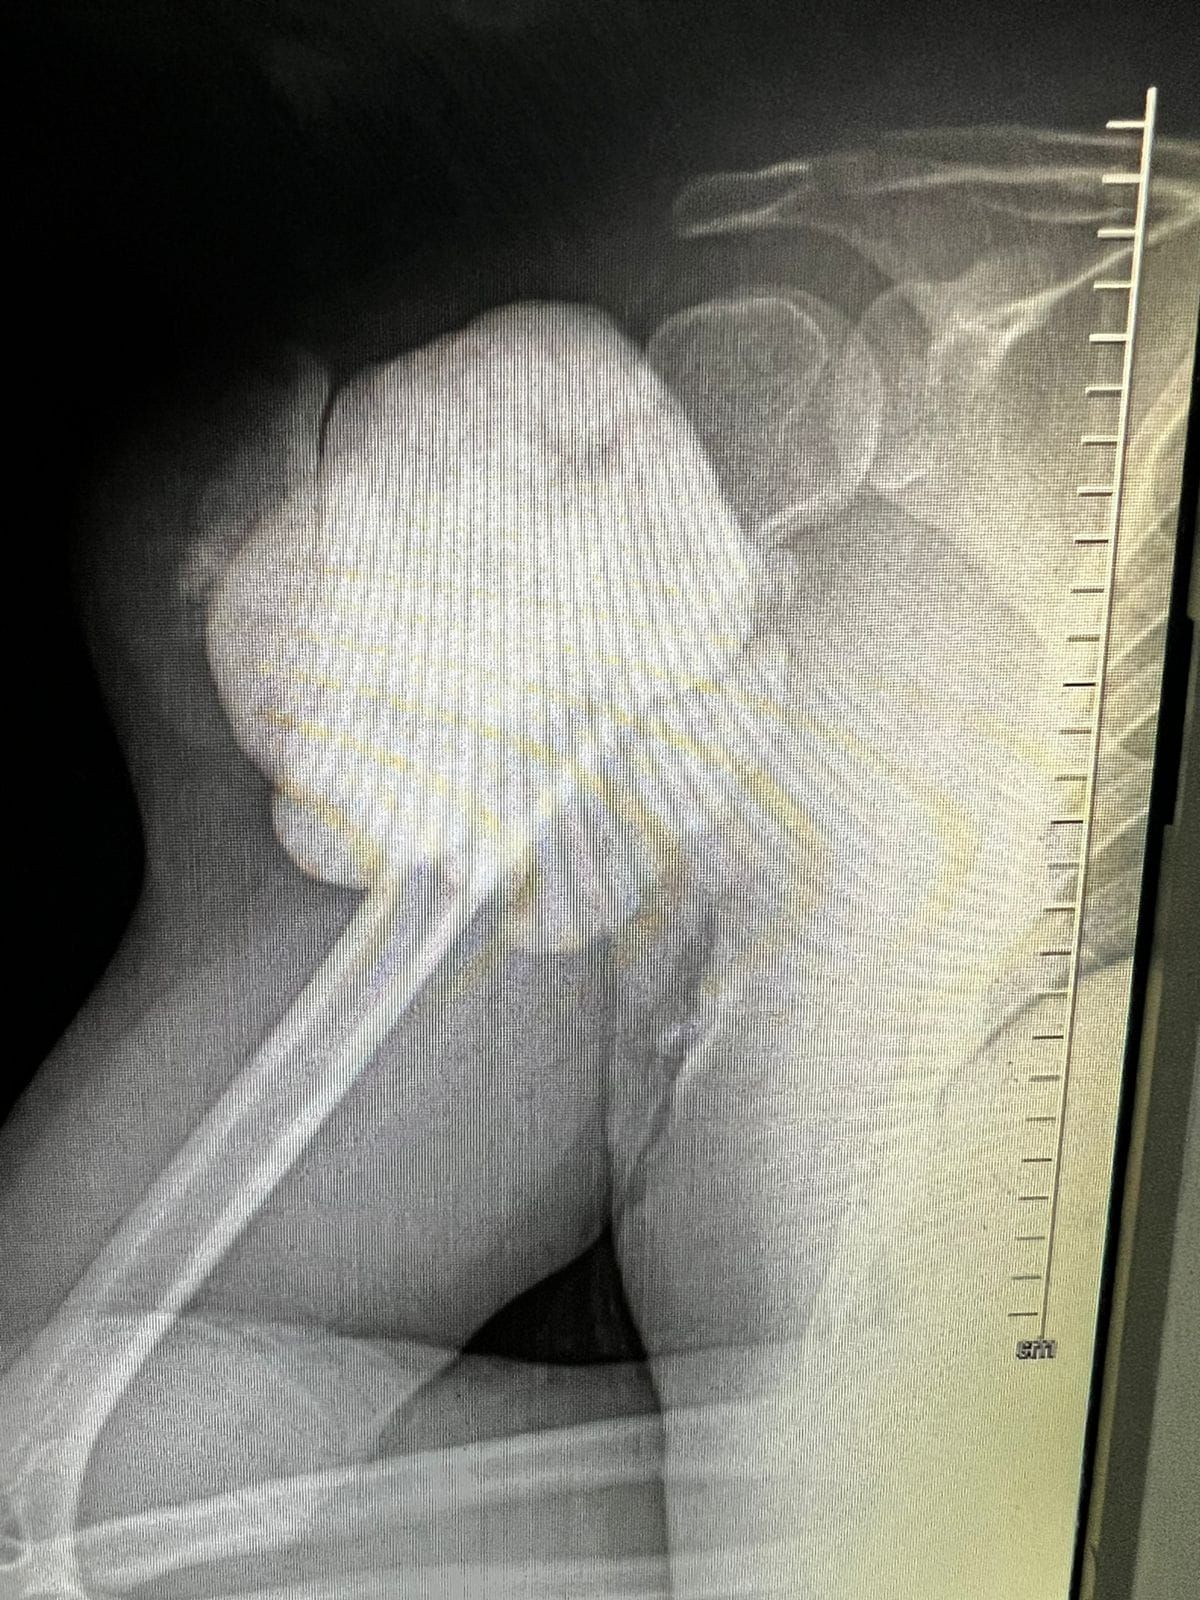

Hola, soy médico egresado de la BUAP y he tenido el honor de especializarme en Traumatología y Ortopedia en el complejo médico Magdalena de las Salinas, IMSS, con la validación de la UNAM. Además, tengo un Máster en Ciencias Médicas, centrado en el área quirúrgica de tumores músculo-esqueléticos, también en la Unidad Médica de Alta Especialidad, Magdalena de las Salinas.

• Tumores oseos

Tumores Músculo Esqueléticos

• Tumores Músculo Esqueléticos Cirugía de rodilla  •